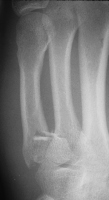

Case 4

Rotated unstable spiral oblique proximal phalanx

fracture. |

| Reduction and fixation. |